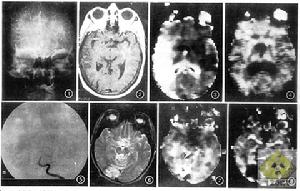

(3)特殊類型的TCIA:近年來隨著CT和MRI在臨床上的廣泛套用,發現多量TCIA患者存在小灶性腦梗死損害,國外學者報導腦CT掃描檢查表現為低密度梗死灶者占10%~40%,而MRI檢查有腦實質改變者可高達84%因而提出應以“有短暫性神經體徵型腦梗死(cerebralinfarctionwithtransientsigns,CTTS)”描述那些臨床上符合TCIA但腦CT掃描或腦MRI檢查顯示有腦梗死的病例

TCIA是腦血管病綜合徵的變異型,可能相當於無腦梗死的短暫性腦缺血或者是臨床迅速完全恢復的小梗死。某一支腦血管反覆缺血發作,可能引起相當部位的腦梗死。部分TCIA患者,如果症狀和體徵持續24h以上,在隨後數天內就會穩定或部分恢復稱之為完全性卒中,而部分患者可以在24h後不斷進展惡化,稱之為進展性卒中腦梗死在病理上是一個由量變到質變的過程,內囊及其周圍結構是腦動脈供血的交界區,常處於低血流灌注狀態加之管壁粗糙管腔狹窄使腦穿通動脈易於形成血栓,進而發生腔隙性梗死。如果影像上發現了梗死灶並且與臨床TCIA一致便可診斷為腦梗死或多發性腦梗死對於TCIA發作腦CT掃描見到腦梗死灶,可診斷為腦梗死,即TCIA型腦梗死這說明TCIA和腦梗死有極其密切的關係。部分TCIA患者腦CT掃描和腦MRI檢查可發現梗死灶因此腦CT掃描是診斷腦梗死最常用最有價值的影像學檢查手段。它可以為臨床及時有效的治療提供依據,所以凡臨床診斷TCIA的患者均應進行腦CT掃描。

7.腦CT掃描、腦MRI檢查不能證實有腦血管病的證據。

4.腦CT掃描或腦MRI檢查主要是排除診斷。